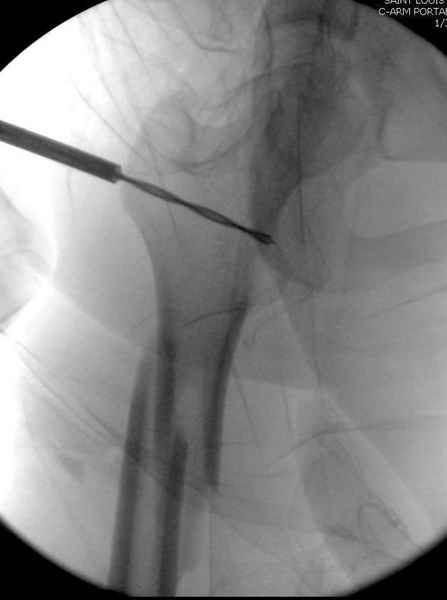

Второй случай тоже репозиция из малого доступа, больному 19 лет, множественные огнестрельные повреждениия конечностей, живота и черепа, правая конечность холодная, без пульсации. Ортопедический диагноз: огнестрельный перелом правого бедра. При срочной ангиографии повреждения сосудов не подтвердилось, конечность из-за ургентности состояния больного зафиксирована временным наружным фиксатором и больной оставлен на операционном столе для срочной лапаротомии хирургической службой.

Больной долго оставался нестабильным, только на 14 день удалось заменить на антеградный интромедуллярный штифт TFN (trochanteric femoral nail) SmithNephew. После неудачной попытки закрытой репозиции, несмотря на использование "joystick", проксимальный стержень от

наружного фиксатора, (перелом начал срастаться) репозицию провели из малого доступа, затем остальные этапы операции.